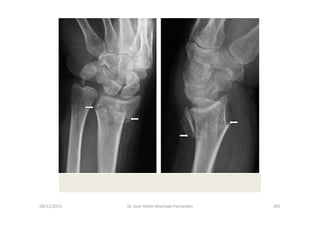

• Instabilidade Escafossemilunar

- Tumefação na face radial do punho

- Hipersensibilidade da face dorsal do punho sobre o ligamento

escafossemilunar

- Teste do deslocamento do escafóide, produzindo crepitação anormal e

reproduzindo a dor do paciente

Fonte: O Exame Físico em Ortopedia – Reider,B.; W.B. Saunders Company